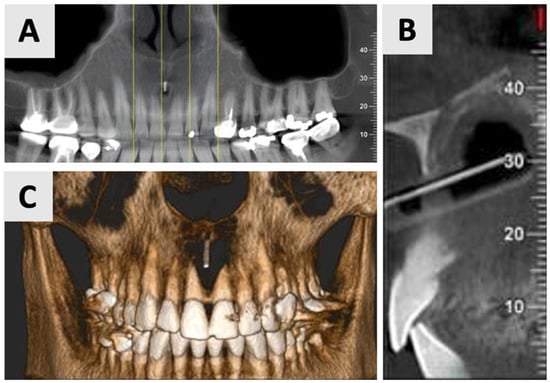

The follow-up examinations at 2 and 16 months post-augmentation revealed favorable bone and soft tissue healing outcomes. CBCT scans were performed at both time points. At the 2-month follow-up, CBCT imaging demonstrated initial bone formation within the augmented site (Figure 6).

Figure 6.

CBCT imaging analysis 2 months post-augmentation. (A) Panoramic reconstruction showing the overall healing of the defect site. (B) The restored contour of the facial and palatal bony walls (blue filled lines). (C) Paraxial view showing the initial osseous regeneration.

By the 16-month mark, significant improvements in bone volume and density were observed (Figure 7). The palatal contour was restored to its proper anatomical form, with notable cortication of the palatal wall. Importantly, there was no evidence of pathological recurrence around the treated teeth. The buccal entry point for the previously placed rubber dam had healed completely, with cortical bone formation.

Figure 7.

CBCT evaluation of bone regeneration at 16 months post-treatment. (A) Panoramic reconstruction showing the absence of radiolucency in the region of prior cyst drainage, indicating a complete osseous integration. (B) Three-dimensional paraxial reconstruction illustrating comprehensive bone regeneration throughout the defect site, with restoration of anatomical contours. (C) Serial axial CBCT slices (through the affected teeth) demonstrate complete reconstruction of both buccal and palatal bony walls, characterized by the presence of distinct cortical bone layers.